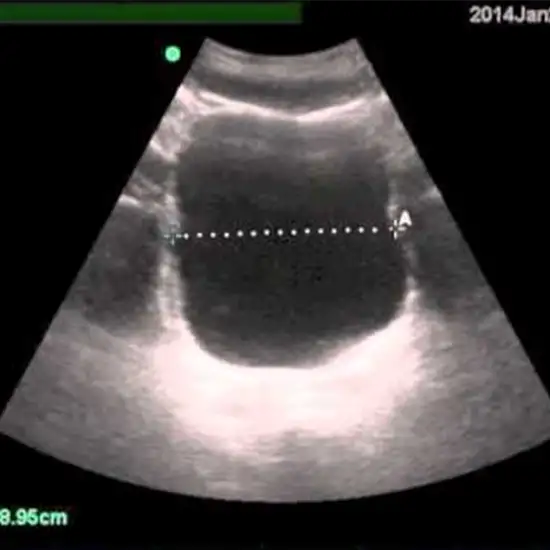

Ultrasound Post-void residual (PVR) residual measurement is a way to figure out how much urine is still in the bladder after someone has gone to the bathroom.

An ultrasound scan for Post-void residual (PVR) is used to determine the presence of residual urine amount after you have attempted to empty the bladder.

The post-void residual ultrasound scan is also known as bladder scanning. The PVR USG scan produces real-time ultrasound scan images in a pain-free, quick, and non-invasive manner that doesn't use any ionizing radiation.